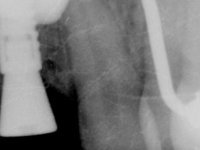

A paciente apresenta um desvio da linha média superior de 6 mm para a esquerda. Resultado da ausência do incisivo central superior esquerdo, os dentes adjacentes inclinaram mesialmente para esta zona, limitando o espaço disponível para a reabilitação prostodontica. Existe uma significativa desarmonia dentária negativa no arco maxilar como resultado da ausência do 21, ausência do primeiro pre-molar com um espaço residual, significativa redução coronária do segundo pre-molar direito, migração dos dentes posteriores para os espaços não preenchidos e uma mesialização molar superior esquerda e direita com uma relação molar em Classe II. Ambos os caninos esquerdo e direito mostram uma relação Classe II na posição de inter-cuspidação máxima. A paciente apresenta uma linha de sorriso média, um biótipo gengival médio grosso, apresenta uma correcta higiene oral sem doença periodontal. Não apresenta hábitos para –funcionais. O exame radiográfico mostra uma significativa inclinação dos eixos dos dentes 11 e 22 com espaço entre a porção apical das raízes. A análise cefalométrica foi feita com o intuito de explorar a hipótese de conseguir arranjar espaço para a colocação de um implante e de uma coroa no local do dente 21. Finalmente a morfologia do osso residual presente na região anterior da maxila foi avaliado com uma TAC, revelando uma perda das dimensões da parede óssea vestibular.

2) Tratamento ortodôntico com o objectivo de criar espaço entre as raízes e as coroas dos dentes 11 e 22,